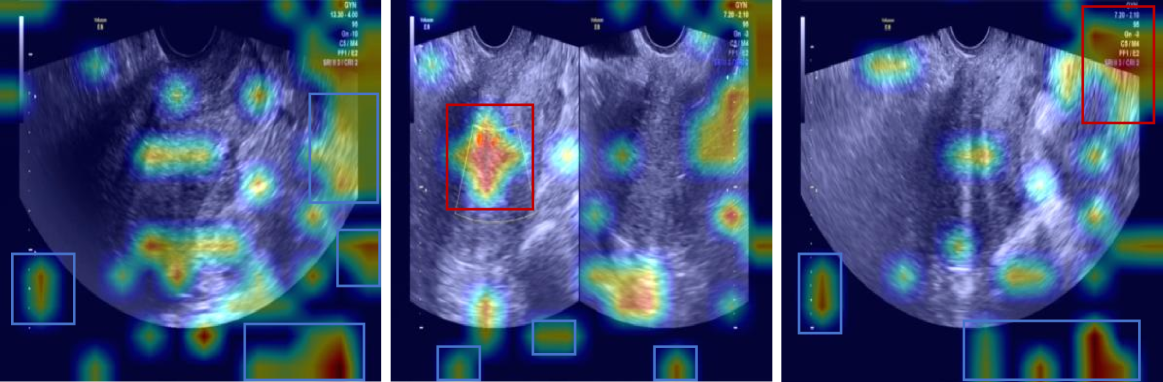

Visualization

To elucidate the internal decision-making process of VLMs, we employed the Grad-CAM heatmap visualization technique proposed by Zhang et al. (cam), where warmer regions (depicted in red) in Figure 6 indicate pixels exhibiting the strongest gradient flow towards the predicted token logit, signifying that the model primarily attends to these semantically significant regions during textual output generation, whereas cooler regions (in blue) receive negligible weight allocation, implying minimal contribution to the prediction; the visualized attention patterns confirm that the VLM’s language reasoning is grounded in semantically relevant visual features such as anatomical landmarks, quantitative measurements, and hemodynamic bar charts—highlighted within red bounding boxes—rather than spurious correlations, yet the model also exhibits attention to non-informative regions including image edges and black areas—highlighted within blue bounding boxes—which lack semantic utility, thereby highlighting a persistent challenge in VLMs: the coexistence of semantic consistency (focusing on task-critical visual elements) and spurious associations (distracting attention to noise or irrelevant artifacts); future work should enhance model robustness and interpretability through strategies such as attention regularization, constrained attention routing, and explicit mitigation of spurious associations.

Refer to caption

(a)

(b)

(c)

(d)

(e)

(f)

(g)

Figure 6: Visualization results. Red boxes highlight meaningful regions, while blue boxes indicate irrelevant or meaningless areas.